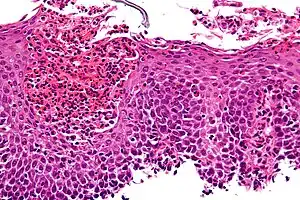

Microscopic Slide of Infectious Esophagitis

Infectious esophagitis

Esophagitis happens due to a viral, fungal, parasitic or bacterial infection. More likely to happen to people who have an immunodeficiency. Types include: